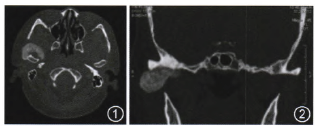

CT:右颞下颌关节有一不规则钙化高密度灶,呈哑铃形。外侧部分类似球形,突破关节腔位于颧弓下方、乙状切迹外侧及髁突前方;中间部分沿关节腔分布,呈盘状,与关节面间有潜在间隙,患例关节腔较健侧明显增宽;内侧部分跨越关节结节向前内斜形进入颞骨鳞部和蝶骨岩部,颅底骨质破坏(图1~3)。

图1CT可见病灶突出关节腔内外侧呈球状生长;图2颞下颌关节间隙不均一的高密度盘状钙化影,钙化影与髁突之间可见潜在间隙,病灶沿关节间隙分布,并向间隙内及外突出;图3病灶向前内突出至颞下窝.钙化物超越关节腔向外突出至面部,向内扩展至颅底;